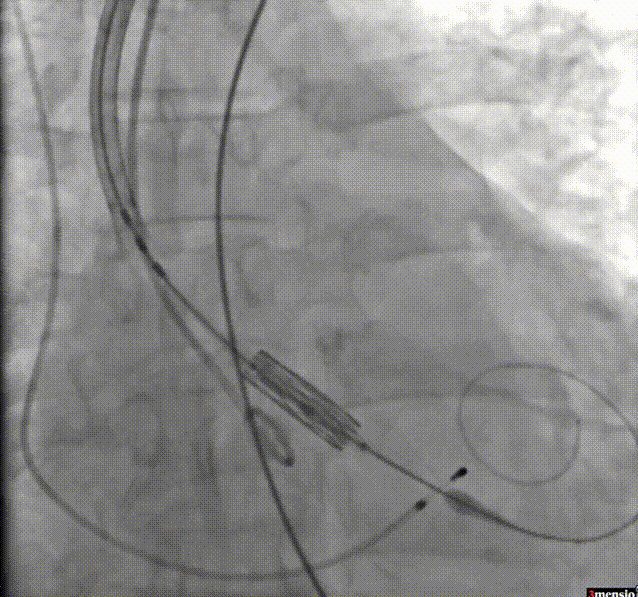

6.调整至共平面角度,瓣膜定位,快速起搏下精准释放瓣膜;

瓣膜定位

瓣膜释放

7.瓣膜释放后造影评估:未见明显反流,无瓣周漏,瓣膜形态和位置满意,双侧冠脉显影良好。瓣膜释放后流入/流出比例 = 100 : 0。瓣膜释放位置:90/10;

瓣膜释放后造影